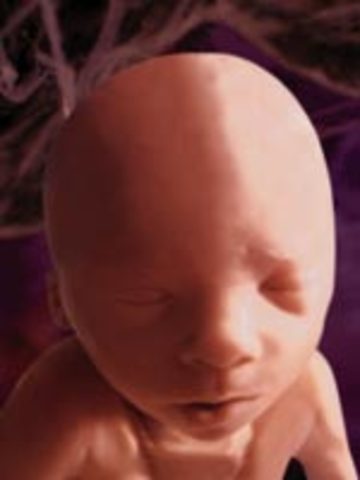

The fetus starts to move. the face begin to look like a baby face.

• Week Thirteen: Baby flexes and kicks

Week Thirteen: Baby flexes and kicks

The movements can be measured. the chin and nose are well defined.